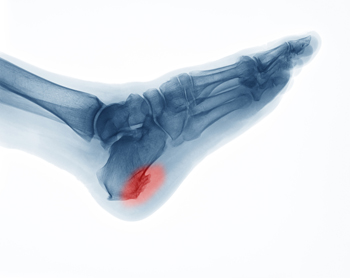

If a calcium deposit should forms between the arch of your foot and your heel, you may have a heel spur. This protrusion may grow gradually, and can be have a hooked, pointed, or even "shelf-like" appearance. Symptoms associated with this condition may include swelling, sharp pains in the heel and surrounding areas, or tenderness that is felt under the heel. If muscle and ligament strain damage the soft tissue in the heel, the result may the formation of a heel spur. Additionally, as the aging process occurs, the heel pads may not provide adequate shock absorption. The symptoms of heel spurs may be similar to those of plantar fasciitis, so it is advised to seek the counsel of a podiatrist who can properly diagnosis this condition.

Heel spurs can be incredibly painful and sometimes may make you unable to participate in physical activities. To get medical care for your heel spurs, contact Brent Harwood, DPM from Southeast Podiatry. Our doctor will do everything possible to treat your condition.

Heels Spurs

Heel spurs are formed by calcium deposits on the back of the foot where the heel is. This can also be caused by small fragments of bone breaking off one section of the foot, attaching onto the back of the foot. Heel spurs can also be bone growth on the back of the foot and may grow in the direction of the arch of the foot.

Older individuals usually suffer from heel spurs and pain sometimes intensifies with age. One of the main condition's spurs are related to is plantar fasciitis.

Pain

The pain associated with spurs is often because of weight placed on the feet. When someone is walking, their entire weight is concentrated on the feet. Bone spurs then have the tendency to affect other bones and tissues around the foot. As the pain continues, the feet will become tender and sensitive over time.

Treatments

There are many ways to treat heel spurs. If one is suffering from heel spurs in conjunction with pain, there are several methods for healing. Medication, surgery, and herbal care are some options.